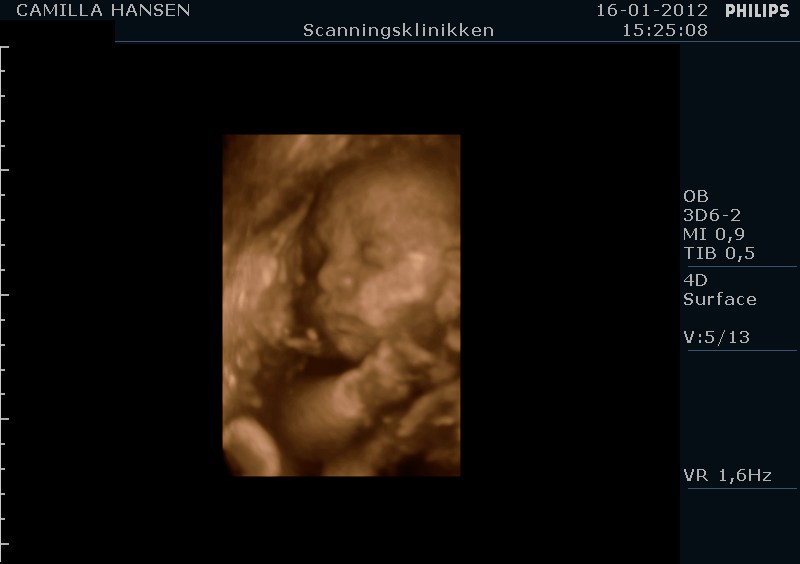

babymus77 skriver:

Ejj hvor er de gode og tydelige 3D billederne:-) Jeg skal her d 20 april, men ved ikk om det er for tidlig?? Er der 26+3???

tak det er nogle rigtige gode billeder.....

jeg var i uge 28 eller 29 og det må helst ikke være sener ind det.

jeg fødte d.26/3 2012 og billederne passer hun ser ud som på billederne.

3d/4d scanninger er helt klart noget jeg vil anbefale.